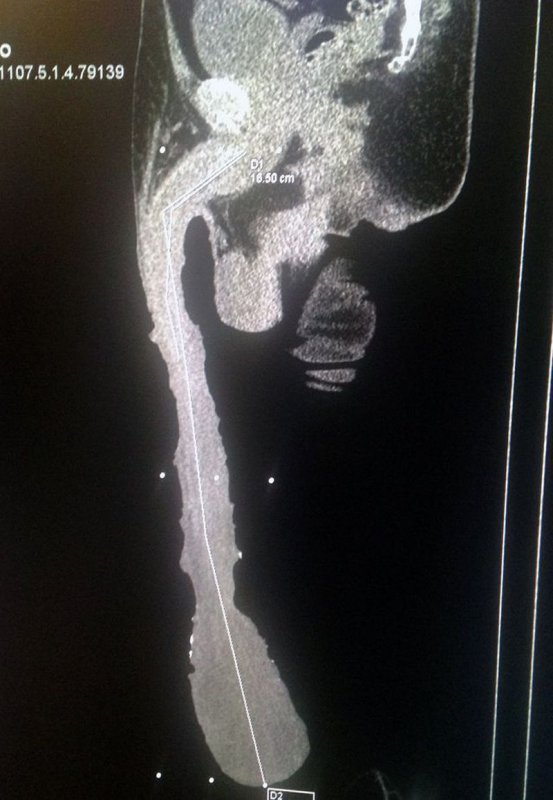

54-летний Роберто Эскивел Кабрера из мексиканского города Сальтильо может похвастаться рекордным размером члена — его длина составляет почти полметра (48 см, если быть точным). От операции по уменьшению пениса он отказался, несмотря на то, что процедура могла бы вернуть его детородному органу функциональность.